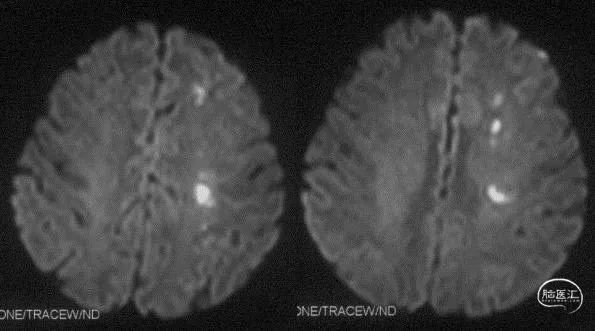

↑↑↑脑核磁提示梗死位于左侧内分水岭区域